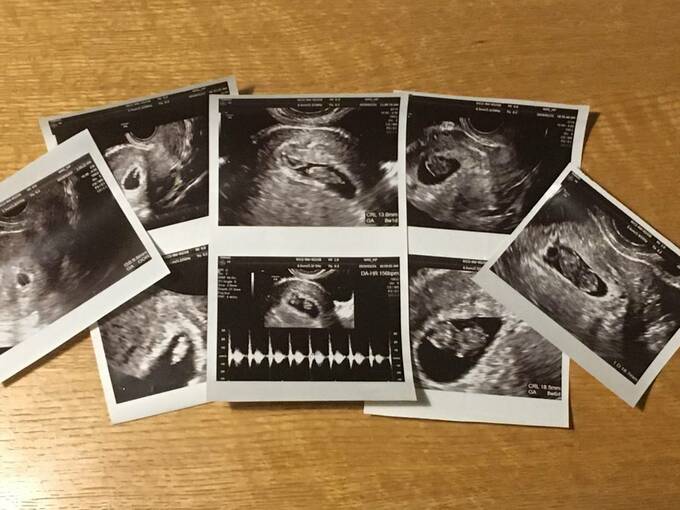

しかし、手術当日も心拍は停止したまま。ASCAさんは20代という若さで、3回連続の流産を体験することになりました。さらに、「不育症対策をしたにも関わらず流産」という事実が追い打ちをかけ、絶望のあまり自殺を考え始めるように。精神科にかかると、「重度のうつ病」と診断されました。

不育症の原因や治療法は研究途上にあり、原因がわからないまま流産を繰り返す人は65%以上にのぼります(厚生労働省研究班不育症研究調べ)。さらに原因が判明したとしても、100%流産を防ぐ治療法は確立されていないのが現状だそうです。ASCAさんもこの経験を機に、自力でさまざまな文献を読み漁るようになりました。

「流産は、女性の体だけでなく心も深く傷つける体験です。なのに『不育症』という言葉も必要な検査も、自力で調べるまで、一般の産婦人科医は教えてくれませんでした。こんなに流産を繰り返す前に、『不育症検査』や『胎児絨毛染色体検査(流産した胎児の染色体異常の有無を調べる検査。結果によって今後の流産対策が大きく異なる)』を受けたかったです」